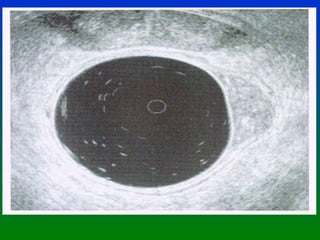

CANCER DE RECTO DIAGNOSTICO ANNALS OF ONCOLOGY SUPLEMENTO OCT. 2002 El Ultrasonido endorrectal es la mejor herramienta Para evaluar la invasión tumoral en la pared rectal. Con un elevado % de sensibilidad y especificidad. UT 1 Invasión hasta la muscularis mucosa UT 2 Invasión hasta la muscularis propia PT 1 Confinado a la grasa submucosa * En estas condiciones la mejor elección es una  Excisión local

CANCER DE RECTODIAGNOSTICO ANNALS OF ONCOLOGY SUPLEMENTO OCT. 2002 El Ultrasonido endorrectal es la mejor herramienta Para evaluar la invasión tumoral en la pared rectal. Con un elevado % de sensibilidad y especificidad. UT 1 Invasión hasta la muscularis mucosa UT 2 Invasión hasta la muscularis propia PT 1 Confinado a la grasa submucosa * En estas condiciones la mejor elección es una Excisión local